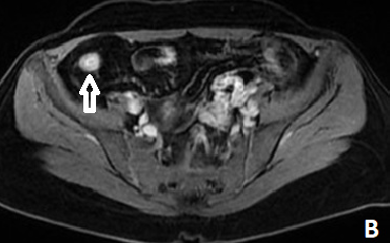

The Fat Halo Sign: A Valuable Imaging Tool for Diagnosing Crohn’s Disease

Yassine Zerhari, Asaad El Bakkari, Hatim Essaber, Soukaina Allioui, Hounayda Jerguigue, Youssef Omor and Rachida Latib. 10(4): 21-23.